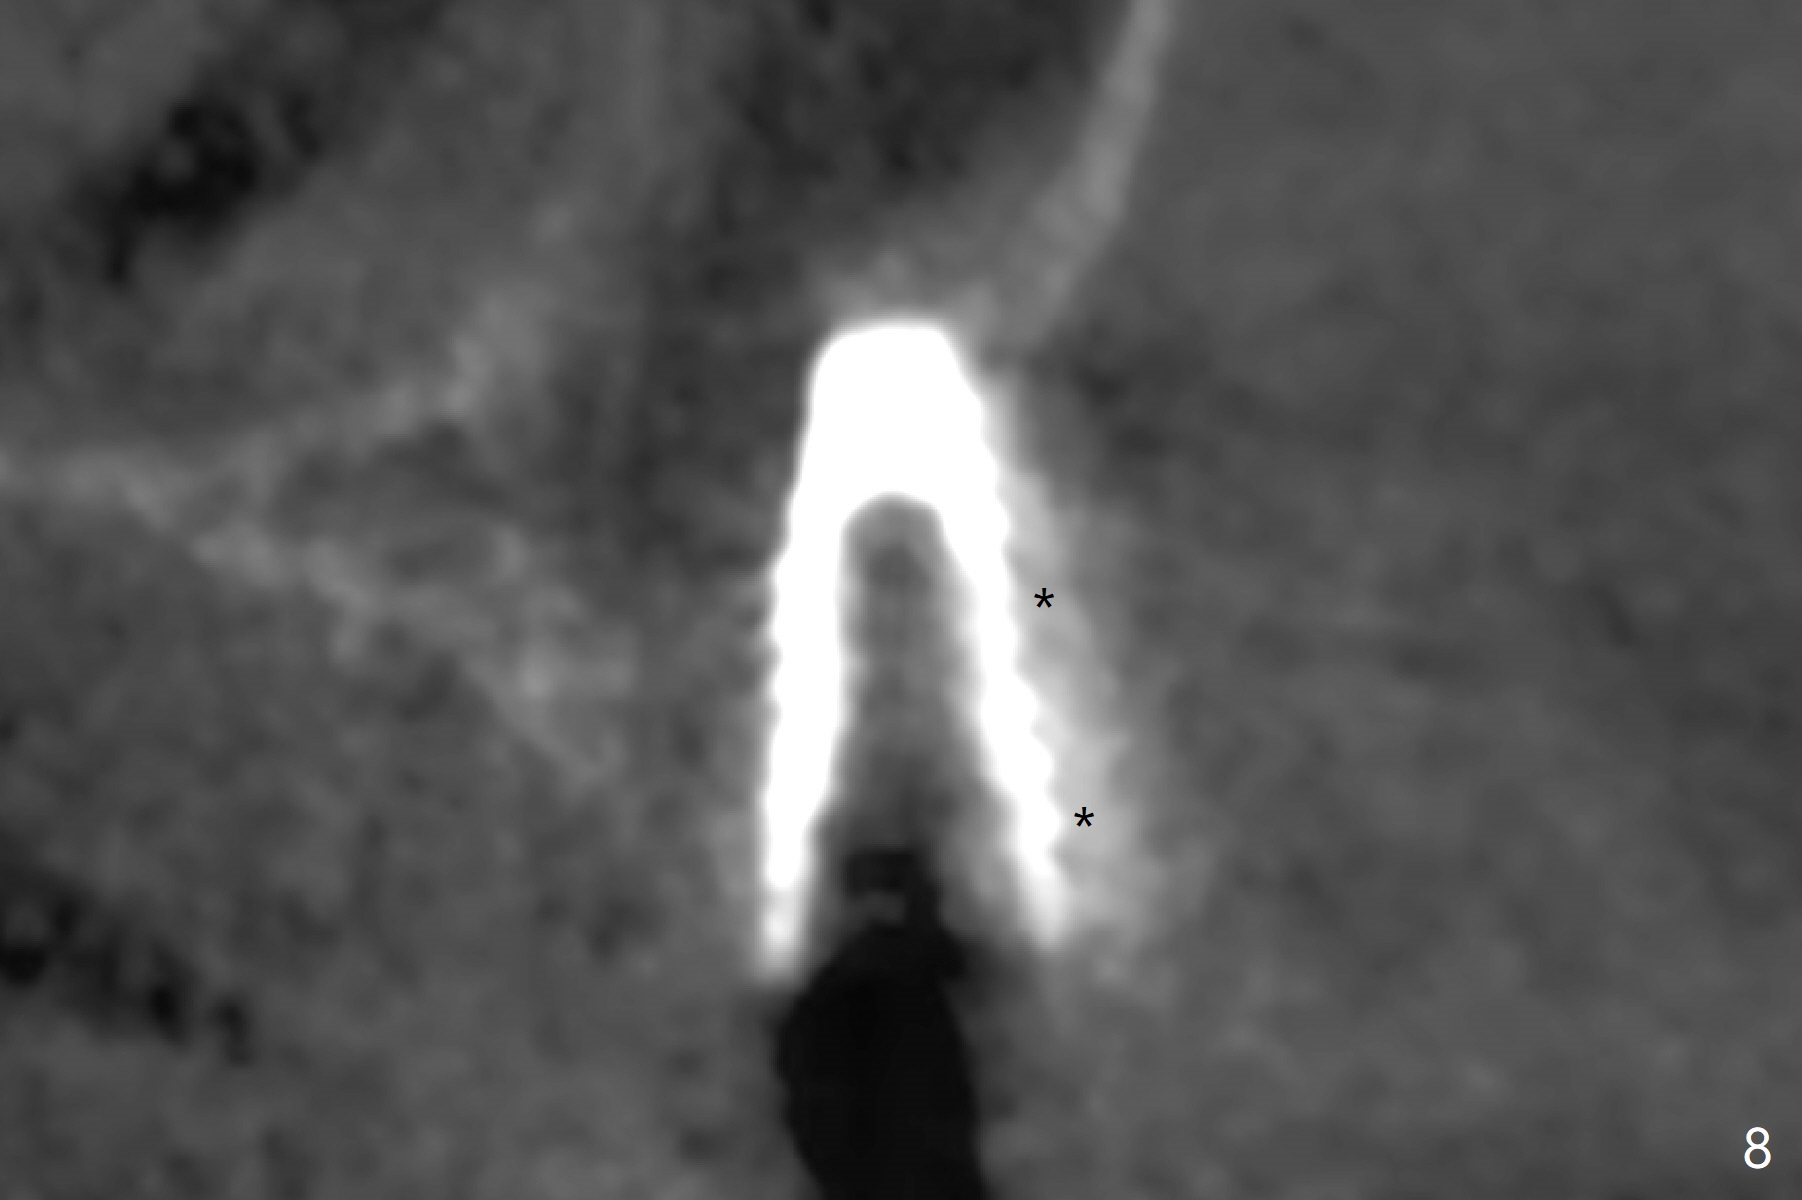

After osteotomy with guide and 2.2 mm drill for ~ 4 mm at #14, a bone expander (1.3/2.3 mm) is used free hand for sinus lift for 12 mm (from the gingival margin, Fig.1; a 10 mm long implant is planned). Following the next expander (1.7/3.1 mm) for the same depth with binding, the sinus membrane is suspected to have perforated. A piece of Osteogen Plug is inserted into the osteotomy as deep as possible with the purpose to repair the sinus membrane (no bone graft being used), followed by placing a 3.5x8.5 (instead of 10) mm implant with insertion torque ~ 25 Ncm (Fig.2,7-9, CT). As compared to preop CT (Fig.4-6), the previously grafted bone is lifted into the sinus by the bone expanders and the implant (Fig.7*). At the same time, the grafted bone has been condensed and pushed buccally (B) (Fig.8,9 *). A 4x6 mm healing abutment is inserted (Fig.3). There is crestal bone loss 6 months postop (Fig.10). Buccal plate atrophy involves the 3 implants in a row (Fig.11). The crown is loose 1 year 8 m post cementation (Fig.12). After proximal reduction, the crown/abutment rotates and sits down substantially (Fig.13). Since the crown is extremely long, it cannot be seated together with the abutment. The latter is seated with X-ray confirmation before proximal reduction of the crown (Fig.14).